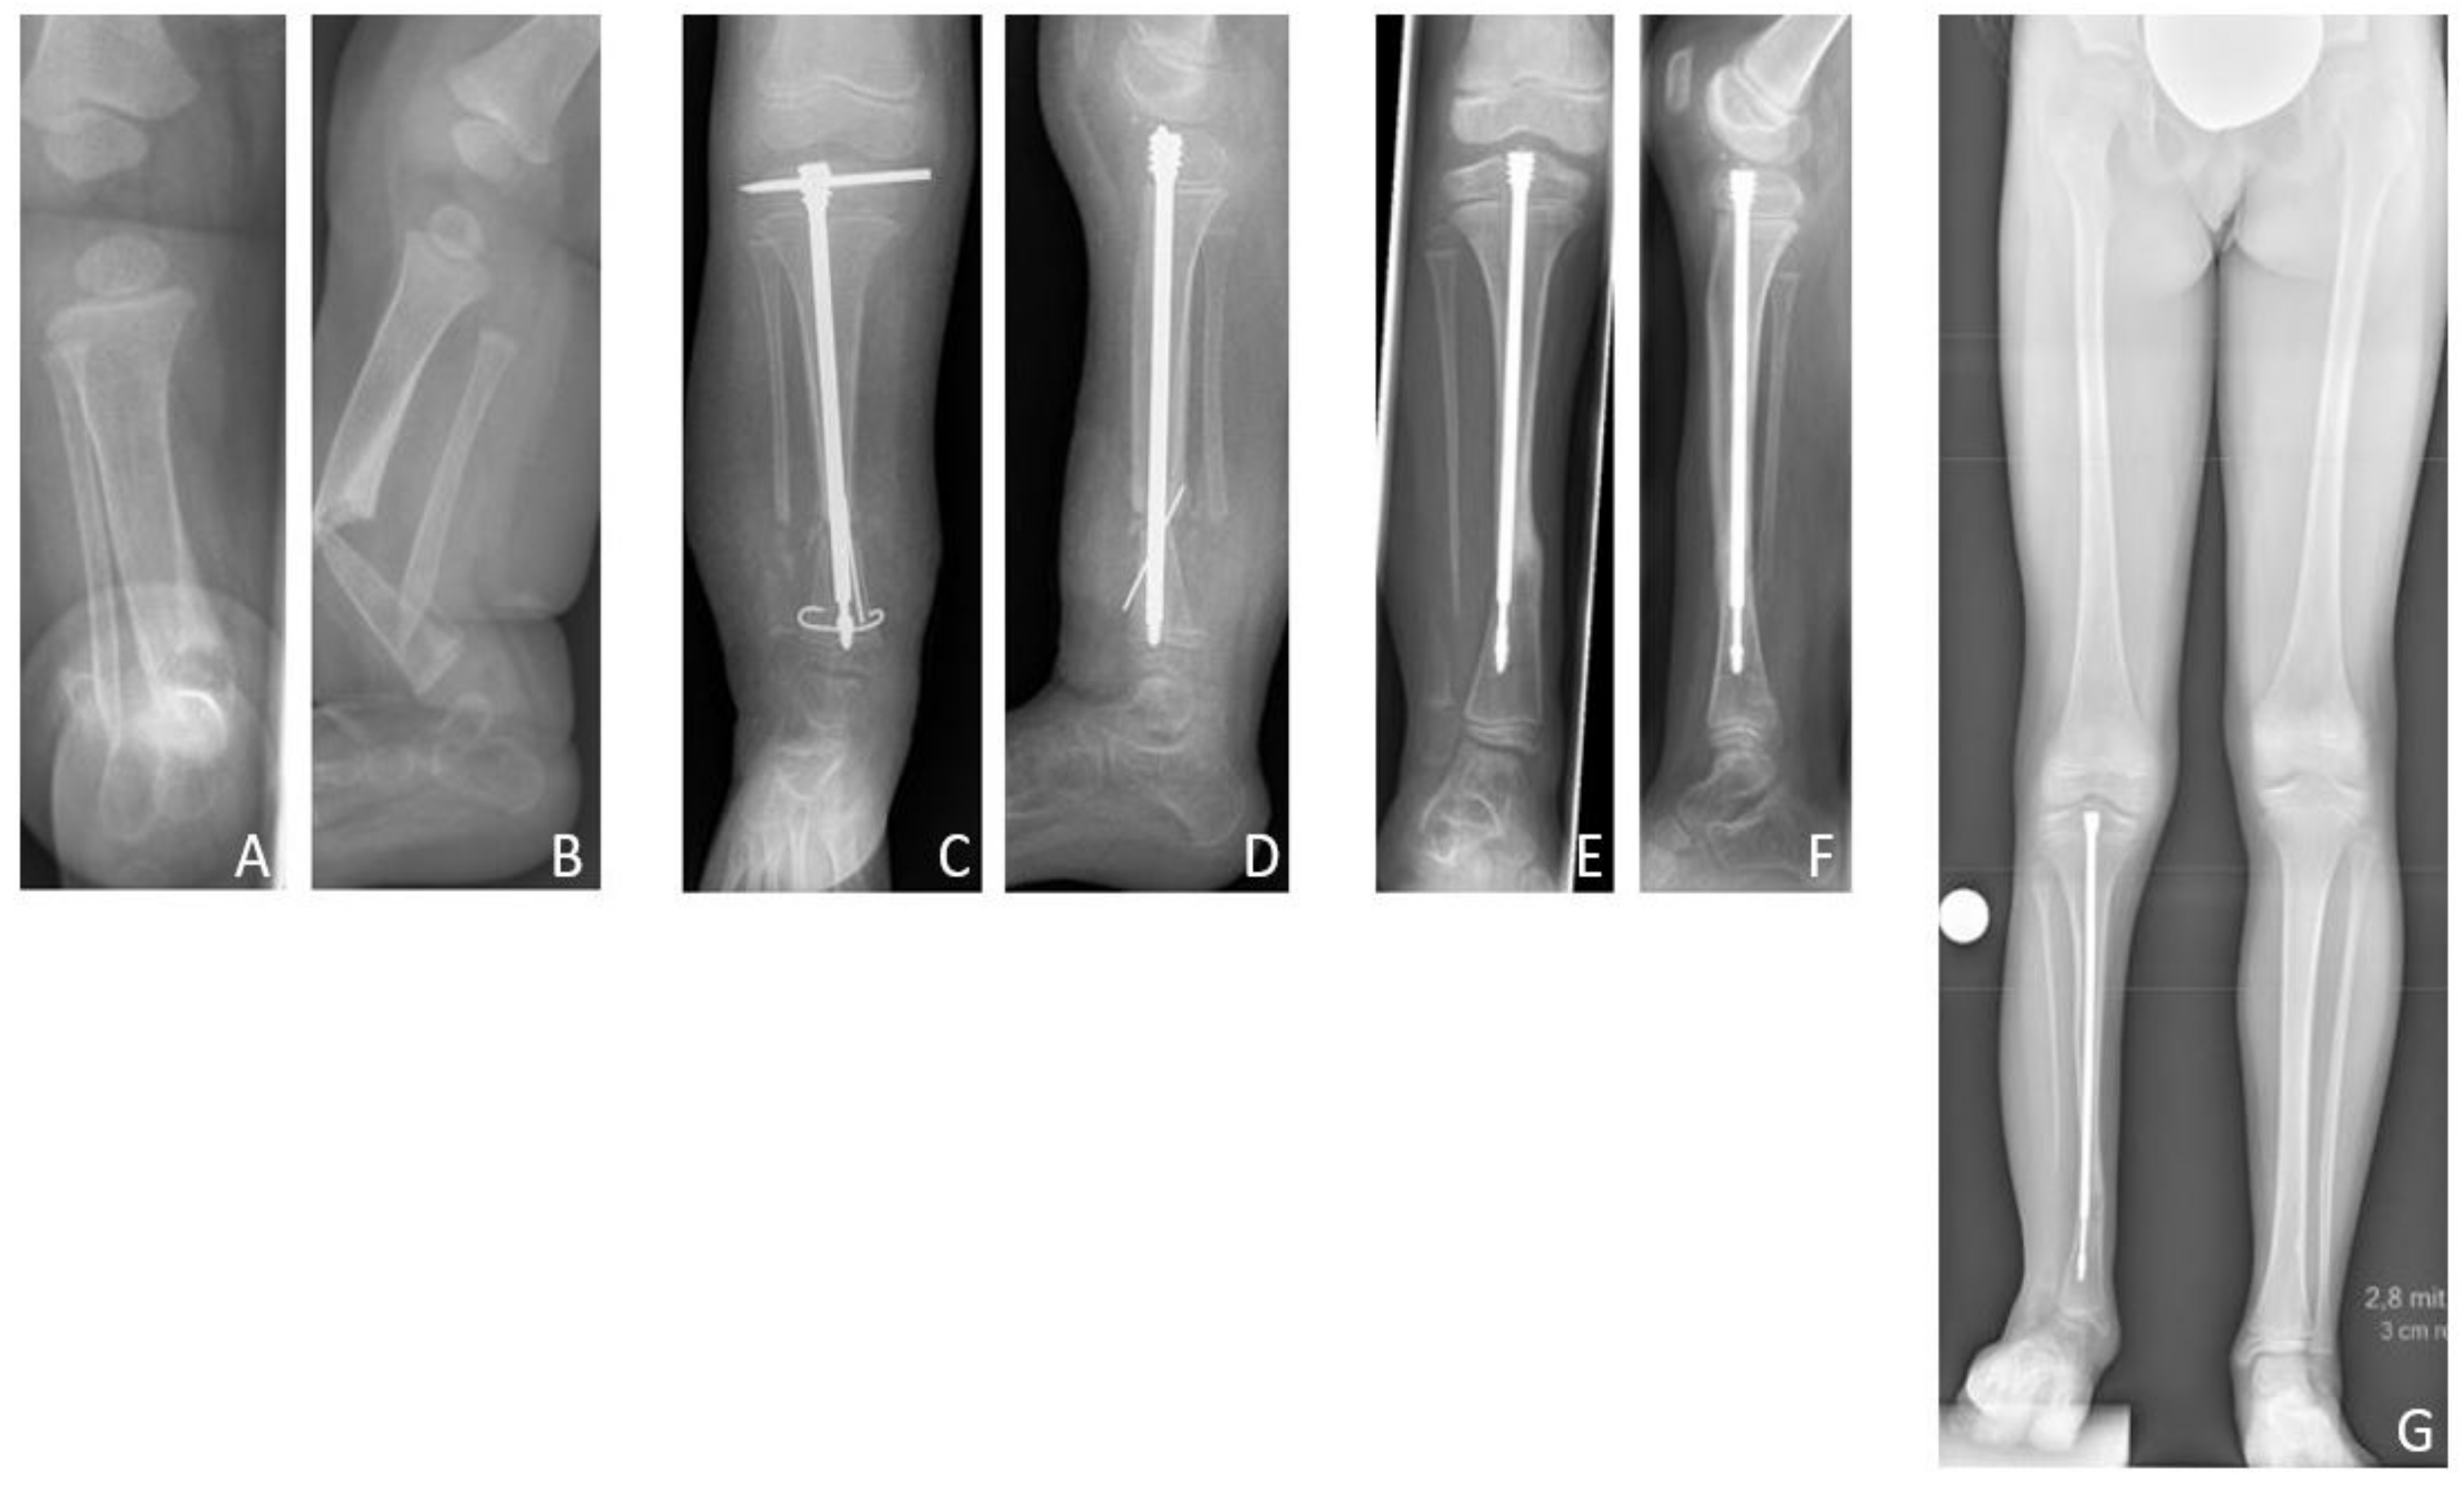

3.4. Results Group C: Intramedullary Nailing

The mean age at first surgery was 7.1 (2.8–14.2) years. Excision of the pseudarthrosis and acute compression before intramedullary stabilization was performed in two cases, while three patients solely received intramedullary nailing for stabilization of the pseudarthrosis site. Four patients (80%) were treated with a Fassier-Duval telescoping nail, and one patient (20%) with a TRIGENTM intramedullary nail. Postoperatively a cast was applied for six weeks. Primary bone union was achieved in three patients (60% primary bone union rate). Excision of the pseudarthrosis had been performed in one of the two cases of failed primary bone union. There were no refractures (0% refracture rate), thus the long-term bone union rate was also 60%. Both patients who failed to achieve primary bone union neither achieved secondary bone union, and showed persistent pseudarthrosis at the time of last follow-up.

According to the modified Johnston criteria, three results were grade 1 and two grade 3 (

Figure 8).